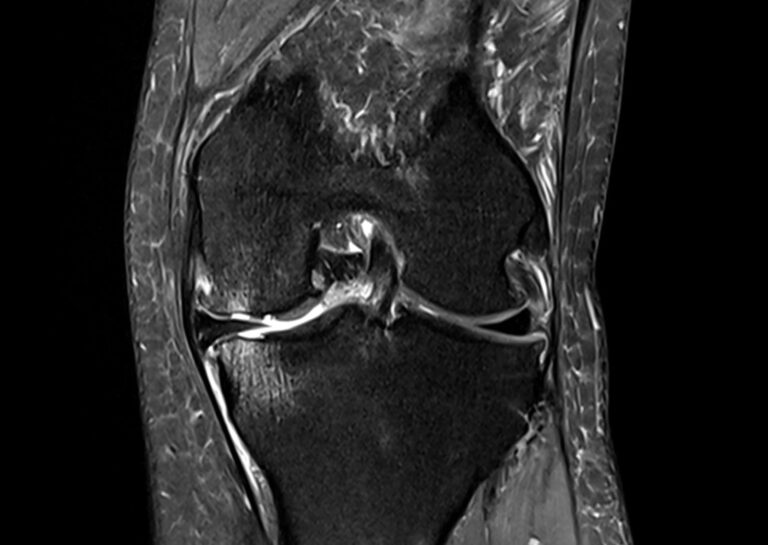

Οι τραυματισμοί υπερχρήσης όπως τενοντίτιδα οστικό οίδημα περιοστίτιδα κνήμης θυλακίτιδα πελματιαία απονευρωσίτιδα έξω και έσω επικονδυλίτιδα μυικές θλάσεις σύνδρομο λαγονοκνημιαίας ταινίας και γόνατο του άλτη εμφανίζονται συχνά όταν η καταπόνηση αυξάνεται πιο γρήγορα από όσο μπορεί να προσαρμοστεί το σώμα ή όταν επαναλαμβανόμενες κινήσεις γίνονται χωρίς αρκετή αποκατάσταση. Η φυσικοθεραπεία στοχεύει στη μείωση του ερεθισμού και του πόνου και στη σταδιακή επανένταξη στη δραστηριότητα με πρόγραμμα άσκησης που βελτιώνει την κινητικότητα την αντοχή και τη δύναμη στην περιοχή που ενοχλεί. Παράλληλα δίνεται έμφαση στη σωστή τεχνική στην εργονομία και στην προοδευτική αύξηση της έντασης ώστε να μειώνεται ο κίνδυνος υποτροπών και να επιστρέφετε με ασφάλεια σε εργασία άσκηση και αθλητισμό.